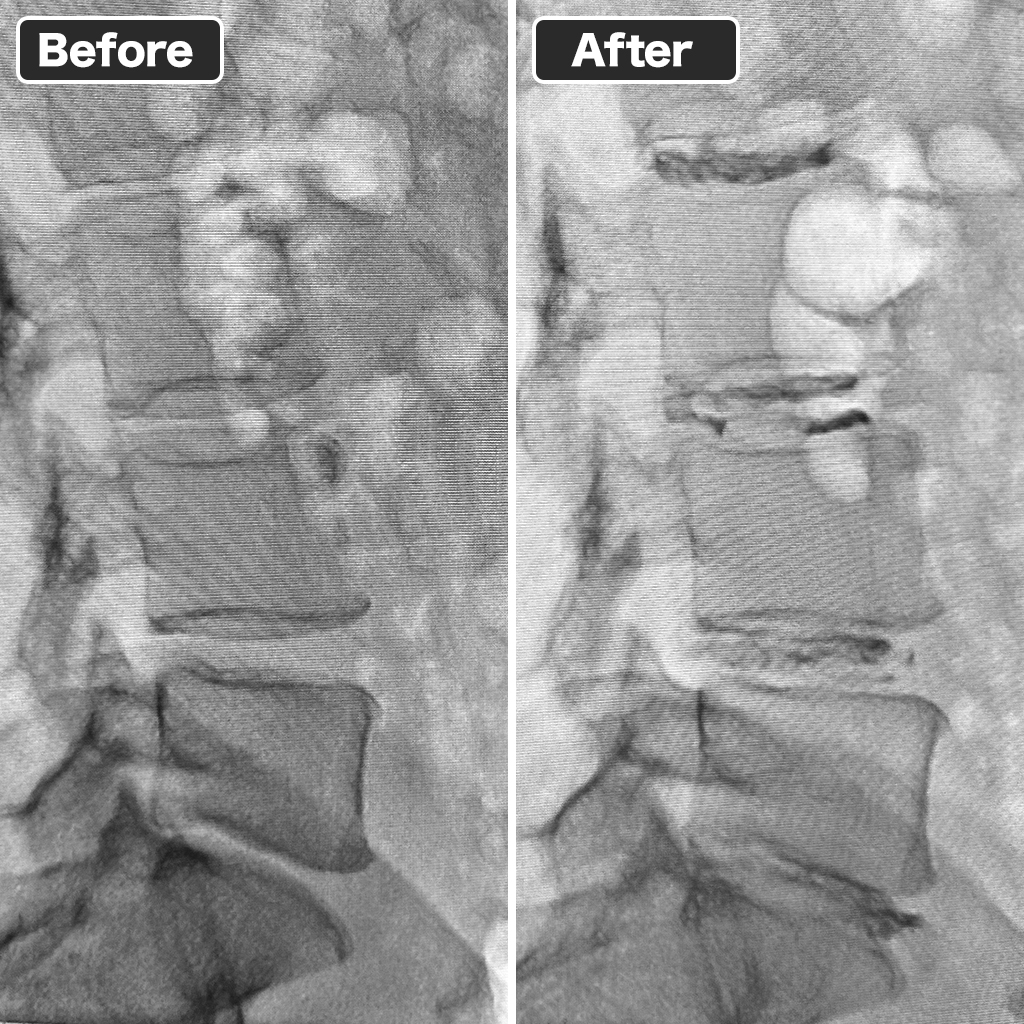

Pre- and Post-Treatment X-rays

We successfully performed the Discseel® Procedure on four discs, ensuring proper repair.